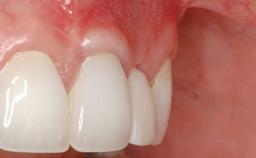

Soft-Tissue Volume Augmentation Using a Connective-Tissue Graft Harvested from the Maxillary Tuberosity

Soft Tissue Grafting Simultaneous